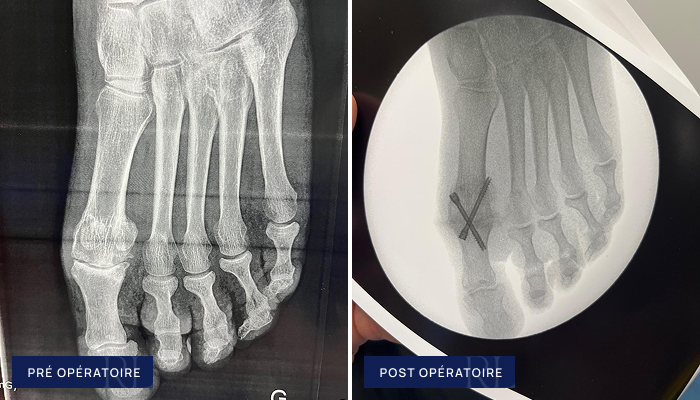

Hallux Rigidus (conservateur)

À gauche : Usure débutante à moyenne de l’articulation du gros orteil (arthrose de l’articulation métatarso phalangienne de l’hallux )

À droite : Décompression articulaire du gros orteil (ostéotomie percutanée)